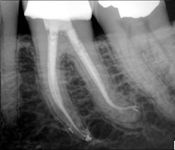

Pictured: Necrosis and 3 Year Recall with Complete Root Formation after Revascularization

Our patient developed necrosis of tooth #9 caused by intrusive luxation. We opted to treat with revascularization with triple antibiotic and MTA. In our 3 year recall, the patient had achieved complete root formation.